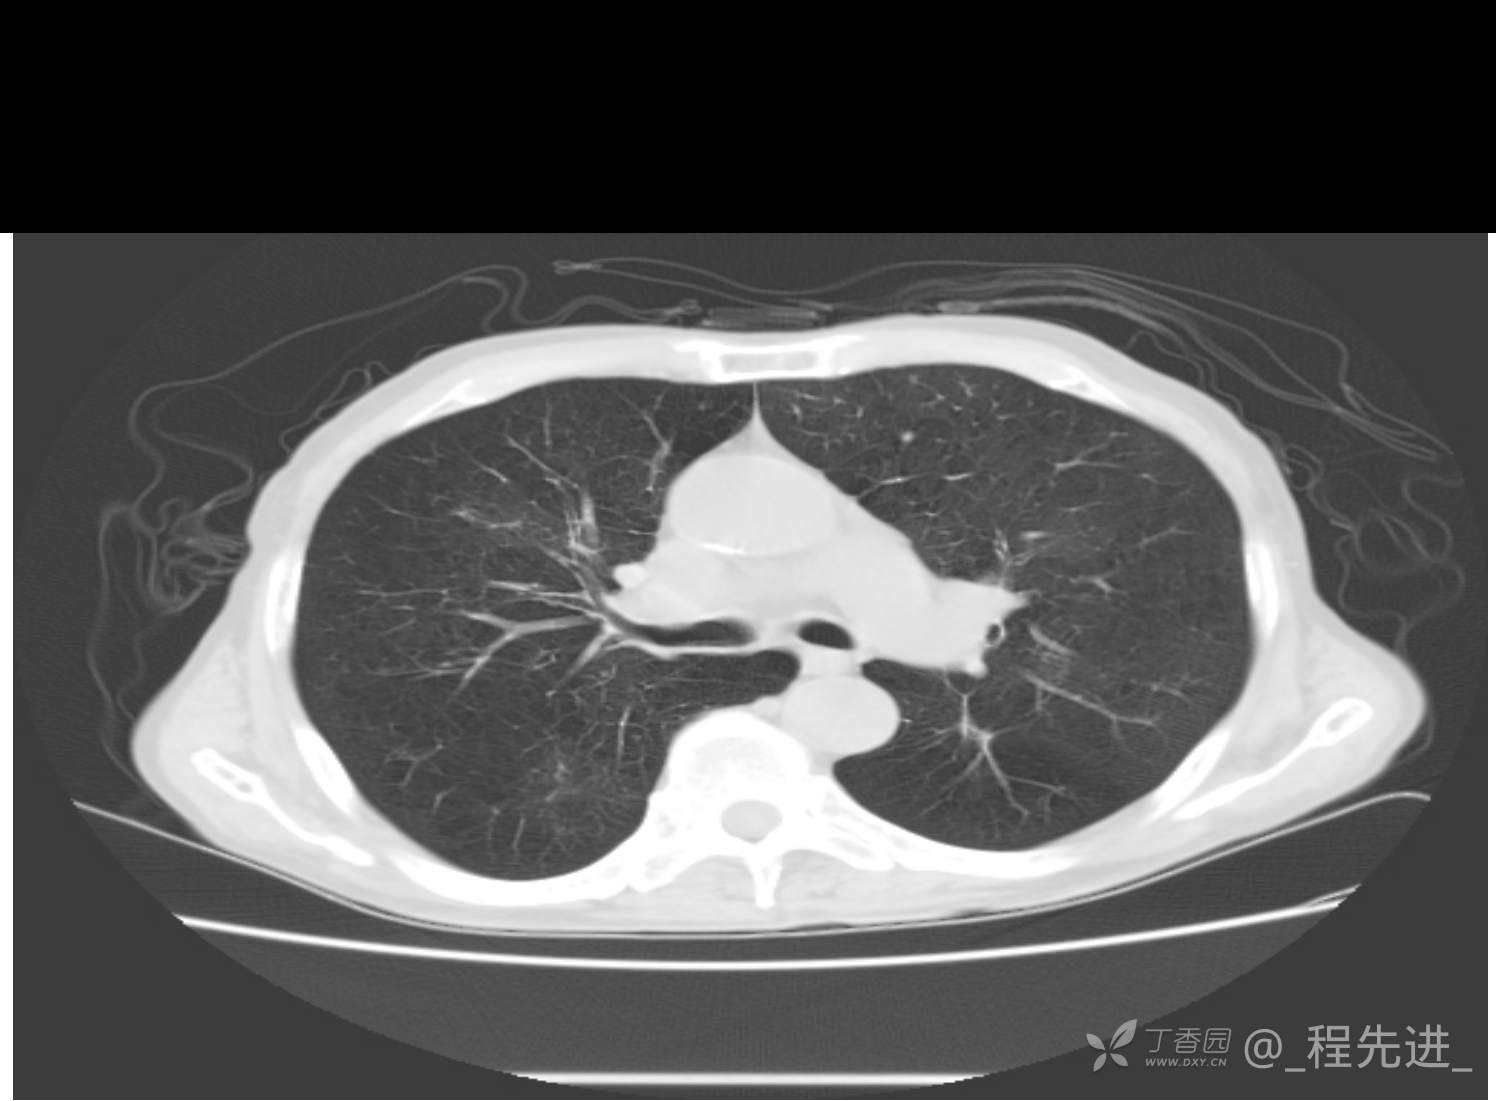

患者性别:男

患者年龄:81岁

简要病史:反复咳嗽、咳痰20余年,加重1周。两肺呼吸音低,可闻及散在干湿啰音。